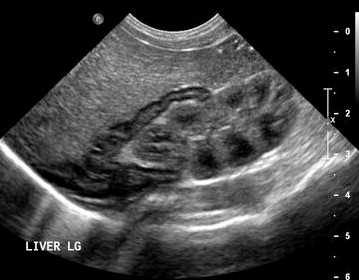

Тимус - киста, B-режим

[EN] Эхограмма №736: Киста тимуса (левой доли) у ребенка 2 лет. Микроконвексный датчик 4-9 МГц (неонатальный), двойной B-режим (слева - продольно, справа - поперечно).

Автор: Суханов С.А., Саратов.

Изображение получено с помощью УЗ сканера H60 (снят с производства).